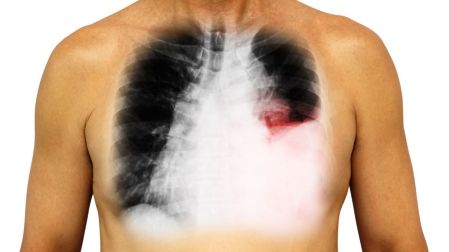

Durante décadas, el diagnóstico de cáncer de pulmón fue sinónimo de tratamientos duros y agotadores, casi siempre ligados a la quimioterapia intravenosa. Para el paciente, esto significaba efectos secundarios intensos, hospitalizaciones recurrentes y una calidad de vida mermada; sin embargo, un giro científico podría dar luz a los pacientes que padecen el cáncer más letal de todos los cánceres.

Hoy, gracias a la medicina molecular, la lucha contra el cáncer de pulmón dio un salto asombroso: tratamientos dirigidos que vienen en forma de pastillas orales. Estos fármacos no solo logran controlar la enfermedad, sino que devuelven la esperanza de una vida más estable y normal a miles de pacientes.

En el subtipo más común, el adenocarcinoma (que afecta al 85% de los casos), los oncólogos buscan una alteración crítica: la mutación del receptor de factor de crecimiento epidérmico (EGFR).